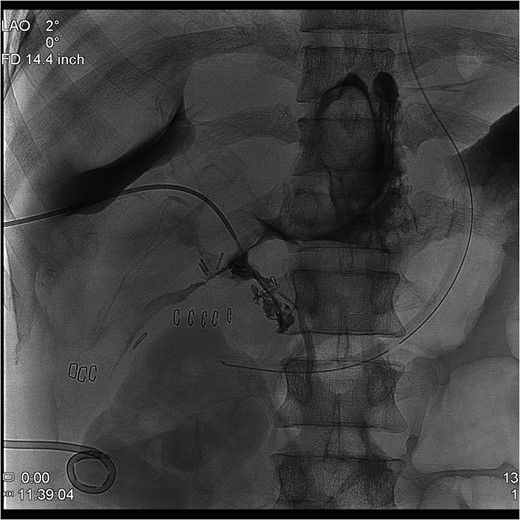

The PTC study confirmed the presence of a completely transected duct, and, fortunately, the ductal injury was traversed with a wire with entry into the distal ductal orifice and into the duodenum (Figs 4–6). Following the procedure, the patient was taken directly to the operating room for open surgical repair.

Percutaneous Transhepatic Cholangiogram with wire traversing into the distal common bile duct orifice. Note duodenum filling with contrast.